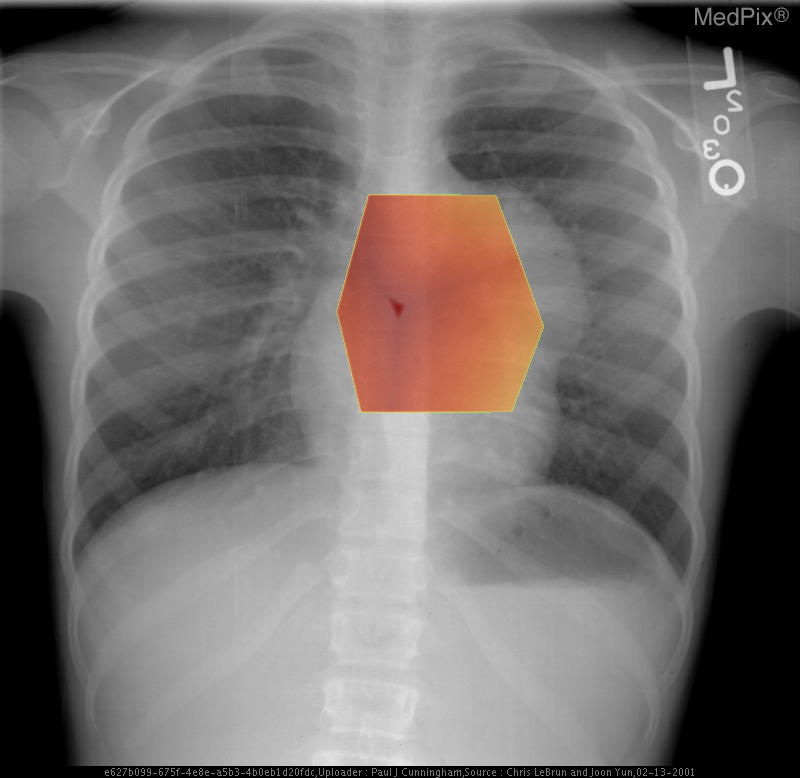

Base slice Focus overlay CLIP overlay

Low confidence

High confidence

1) Findings:

- Frontal chest radiograph, properly oriented: image-left = patient-right.

- Cardiac silhouette is mildly displaced toward the image-right (patient-left), suggesting mass effect from a mediastinal lesion.

- A well-circumscribed, rounded opacity occupies the image-left (patient-right) upper mediastinum, with smooth margins.

- The lesion shows heterogeneous internal density, including areas of relative lucency (suggesting fat) and opacity (possibly soft tissue or calcification).

- Lungs otherwise clear without focal consolidation or effusion.

- Bony thorax intact with no visible rib destruction or vertebral abnormality.

- Trachea slightly deviated toward image-right (patient-left), consistent with mild mediastinal shift.

- Diaphragms symmetric; cardiopericardial silhouette otherwise unremarkable except for mass effect.

2) Most likely diagnosis and why:

Anterior mediastinal teratoma. The well-defined, heterogeneous mass in the anterior mediastinum with soft tissue and possible fatty or calcific elements is characteristic of a mediastinal teratoma. Leftward (patient-left) cardiac displacement and tracheal shift support a space-occupying lesion in the anterior mediastinum. Context consistency: Consistent. The reported age (child) and sex (female) align with a known demographic pattern for benign mediastinal teratoma. Confidence: 90%.